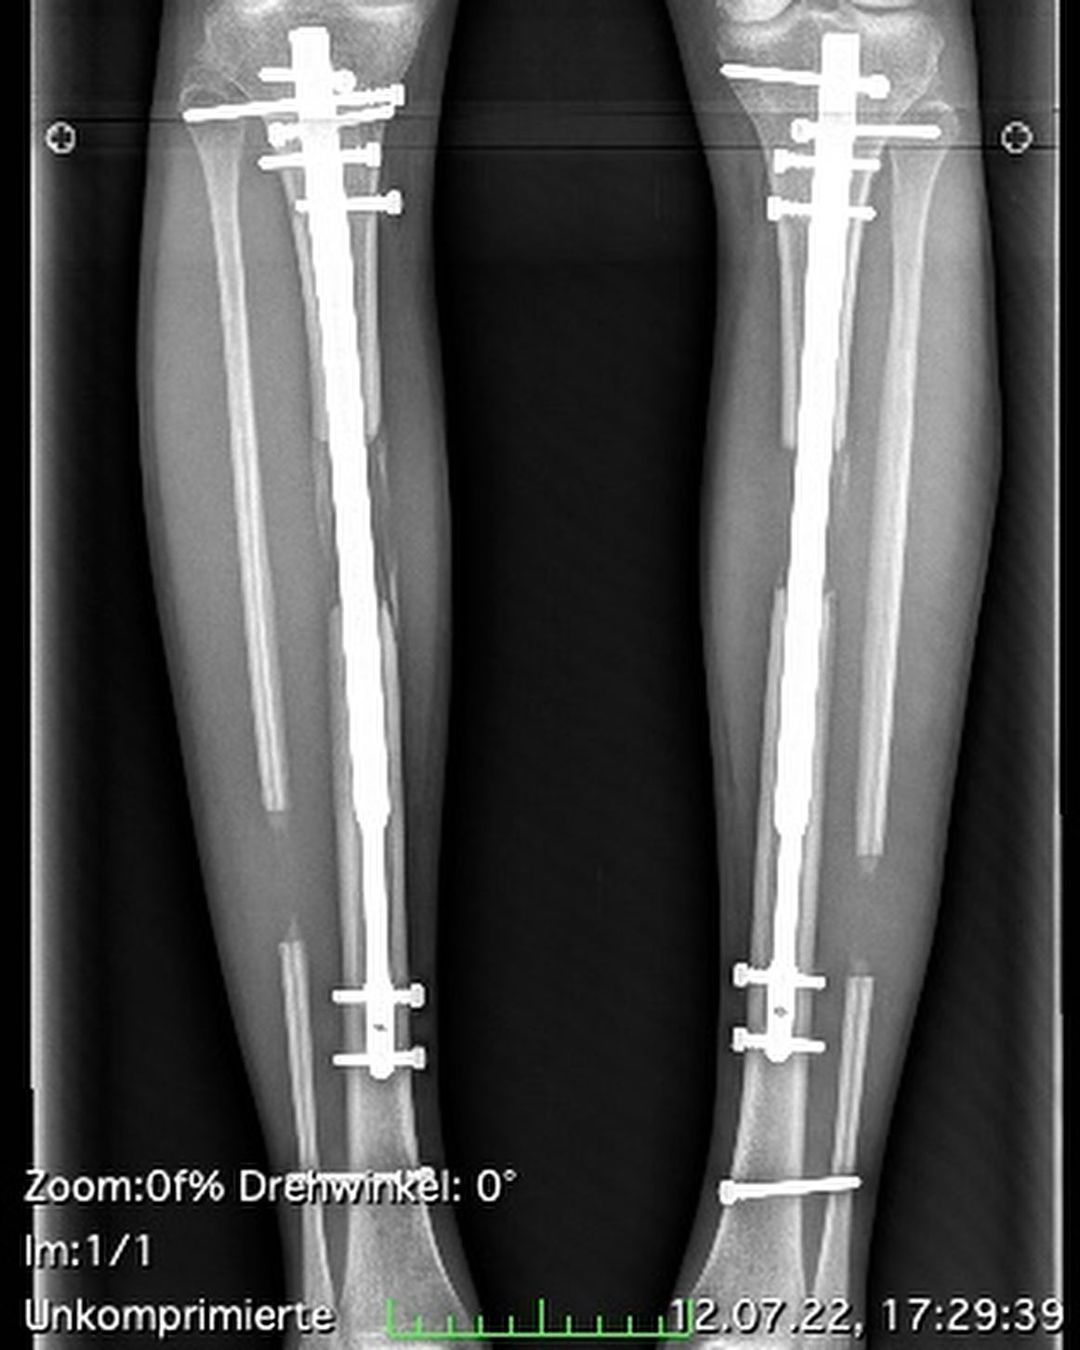

Стоит отметить, что такая операция является сверхсложной Во время нее ломают 2 кости пополам, затем в каждый конец бедренной или большеберцовой кости вставляют гвозди, которые в течение нескольких недель медленно отделяют магнитами, пока они не заживают естественным путем. В результате бедренная кость становится длиннее.

Модель в сети рассказала, что наконец завершила свой путь по удлинению ног. Она призналась, что испытывала не только физическую боль, но и душевную. 23 июня из тела девушки изъяли последние гвозди и теперь ее ноги полноценно стали длиннее на 14 сантиметров.

Как девушке делали ноги длиннее / Фото из инстаграма @theresiafischer